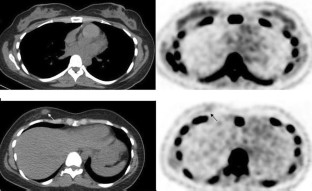

NaF positron emission tomography/computed tomography (PET/CT) images of 69 newly diagnosed breast cancer patients were reviewed. F-18 fluoride uptake as maximum standardized uptake value (NaF SUVmax) was measured in the primary tumor, enlarged axillary lymph nodes and contralateral normal/non-tumoral breast tissue. Low-dose CT images were reviewed to locate the primary tumor and grossly assess its calcification and check for ipsilateral axillary lymphadenopathy. Whole body NaF PET/CT images were reviewed to search for bone metastases. Eighteen patients also underwent F-18 fluorodeoxyglucose (FDG) PET/CT study.

Results

The primary breast tumor was clearly seen as focal or diffuse uptake on NaF PET images in 27 of 69 patients (39%) (mean NaF SUVmax: 2.0 ± 1.0). In the rest, there was only mild bilateral diffuse breast uptake. When analyzing images per histological subtype (42 patients, 43 tumors), 14 of 31 invasive ductal carcinomas (IDC) (45%) and 3 of 4 ductal carcinoma in situ (DCIS) were visible on PET. Five invasive lobular carcinomas, 2 invasive mammary carcinomas, and 1 mucinous carcinoma were not visible on PET. Mean NaF SUVmax of contralateral normal/non-tumoral breast tissue was 1.0 ± 0.4. There was no significant difference in mean NaF SUVmax of primary tumor in cases with and without calcification or with and without axillary lymphadenopathy (p 0.892 and 0.957). There was no correlation between NaF SUVmax and FDG SUVmax values of the primary tumors (r 0.072, p 0.797, Pearson correlation).